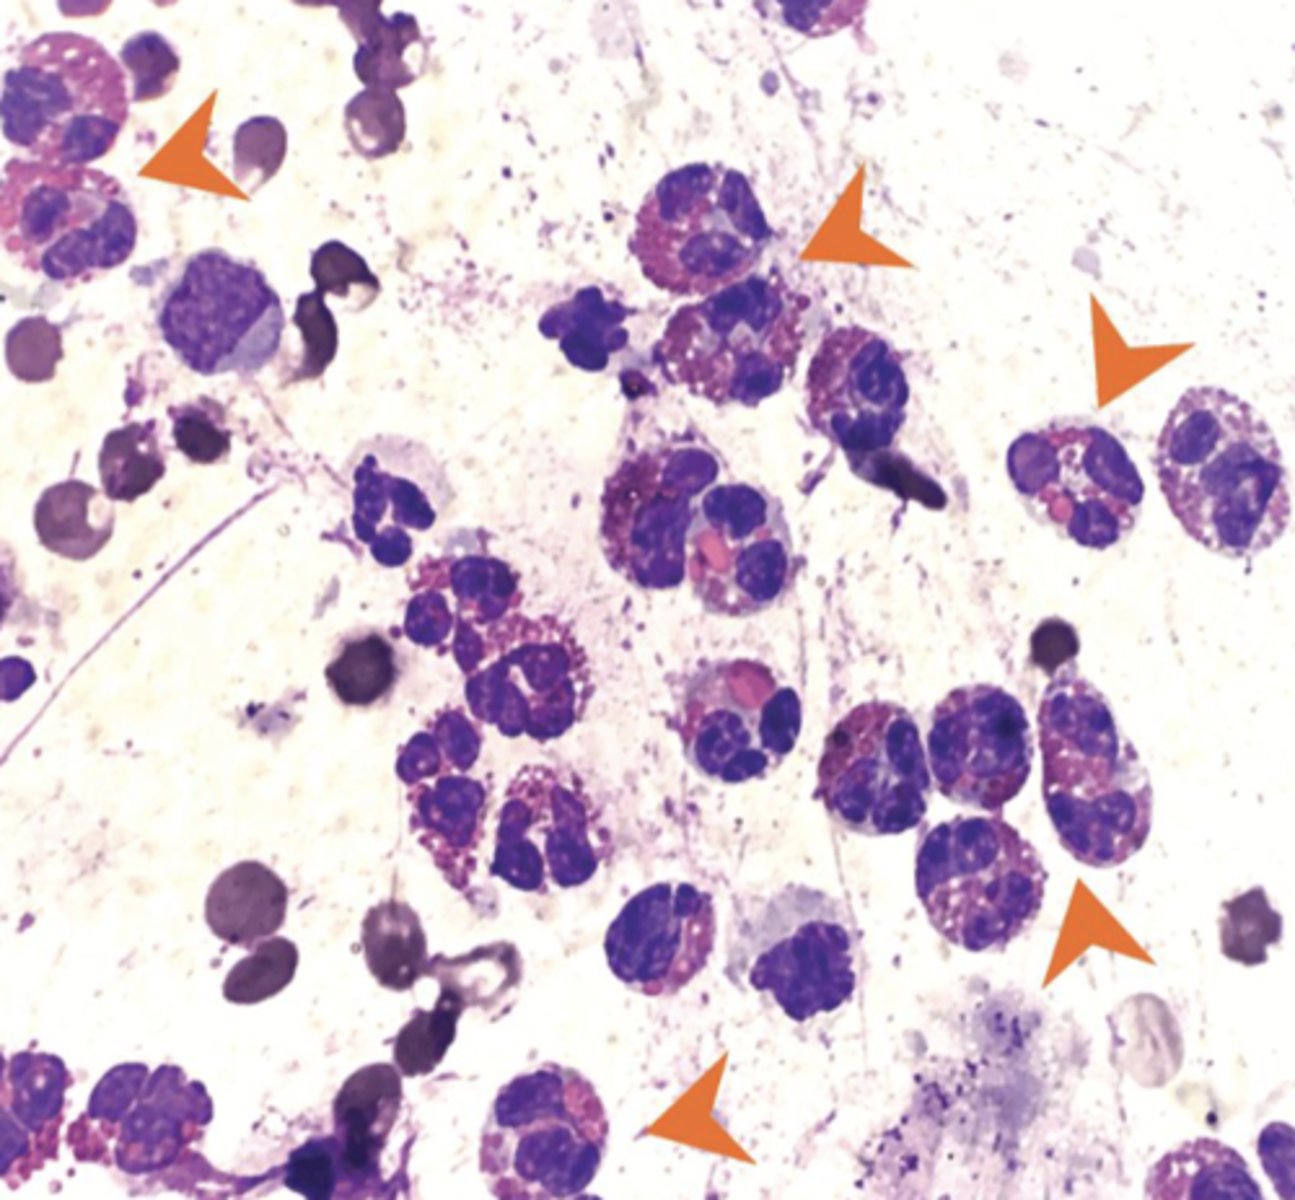

Transmissible Venereal Tumor (TVT)

-cells have a medium to large round nucleus, possibly eccentric

-clumped chromatin, common to see mitotic figures

-multinucleation

-cytoplasm light blue/gray with discrete vacuoles

What type of round cell tumor is this?